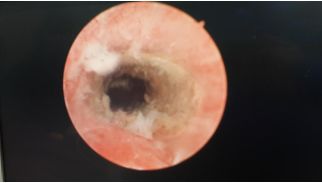

下面附诺舒治疗术后图片:

图2:宫颈与宫腔交界处,消融术不处理宫颈管黏膜